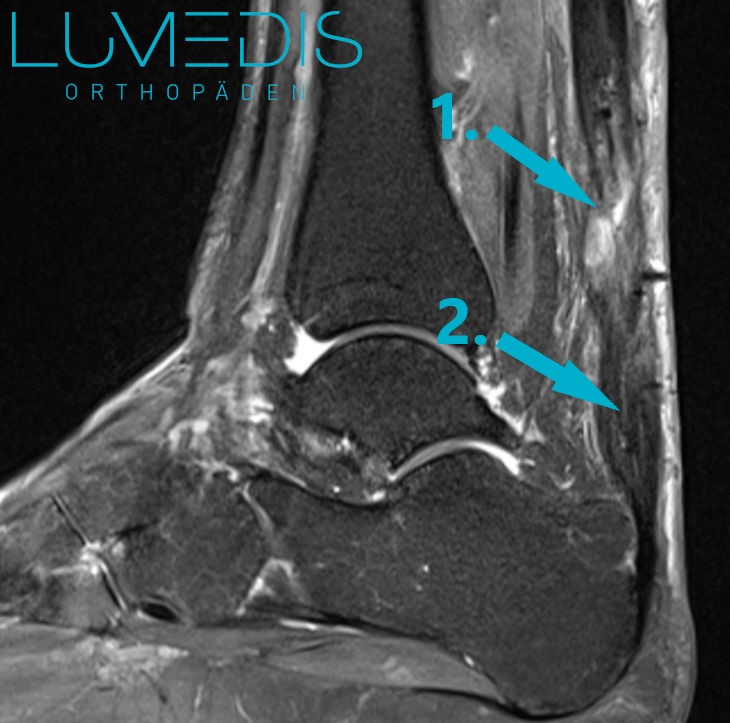

MRT Fuß seitlich T2

Um einn Riss der Achillessehne sicher ausschließen zu können ist eine MRT (Magnetresonanztomographie des Fußes/Sprunggelenks) notwendig.

Auch, wenn die Diagnostik der Achillessehnenentzündung mit Untersuchung und Ultraschall nicht sicher erfolgen konnte, muss eine MRT-Untersuchung angefertigt werden.

Besonders wenn Teilriss der Achillessehne oder Nekrosen (abstrebende Areale innerhalb der Sehne) vorliegt ist eine ergänzende MRT Untersuchung der Achillessehne sinnvoll.

Das MRT ist eine Untersuchung, die Weichteile wie Muskeln, Sehnen und Fettgewebe, aber auch Knochen mit hoher Auflösung darstellen kann, und in der selbst kleinste Hinweise auf Entzündungen, wie minimale Wassereinlagerungen sichtbar werden. Außerdem sind auch feine Strukturen wie Nerven und Gefäße beurteilbar.

Sie ist für den Patienten schonend und kommt im Gegensatz zum Röntgenbild ohne Strahlenbelastung aus.

MRT einer angerissenen Achillessehne